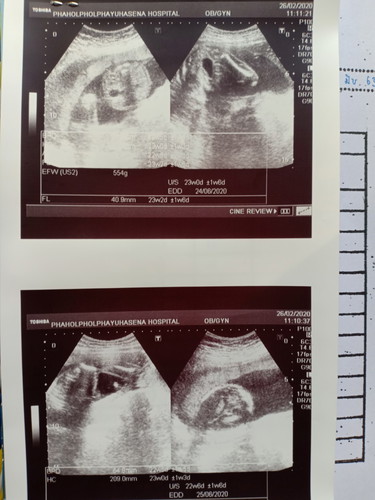

น้องครบ 5 เดือน

ซาวด์ครั้งแรกคะ หมอบอกได้ผู้ชาย อยากรู้ว่าแต่ละภาพเป็นส่วนไหนของน้องบ้างคะ

ภาพที่ 3 ตรวจุดขาวๆ นั้นคือจุดจูของน้องค่ะ